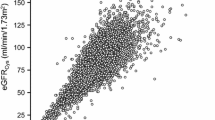

At baseline, the participants’ average age was 60.51 ± 10.03 years, with 6,300 (79.08%) males. The average systolic blood pressure (SBP) and HbA1c were 147.27 ± 20.58 mmHg and 7.57 ± 1.66%, respectively. The eGFRcys, eGFRcr, and eGFRdiff were 88.77 ± 22.73 mL/min*1.73 m2, 93.41 ± 15.43 mL/min*1.73 m2, and − 4.59 ± 18.72 mL/min*1.73 m2, respectively. The eGFR evaluated by serum creatinine and cystatin C showed inconsistent results, with eGFRcys values generally being lower than eGFRcr.

More than half of participants had a baseline eGFRdiff between − 15 and 15 mL/min/1.73 m2 (4679 participants [58.7%]; midrange eGFRdiff); 2280 participants (28.6%) had an eGFRdiff less than − 15 mL/min/1.73 m2 (negative eGFRdiff ), and 1008 participants (12.6%) had an eGFRdiff of 15 mL/min/1.73 m2 or greater (positive eGFRdiff). Compared with the other 2 eGFRdiff groups, participants in the negative eGFRdiff group were older, more often female, with higher baseline SBP, BMI, uACR and more anti-diabetic and antihypertensive treatment (Table 1; Fig. 1).